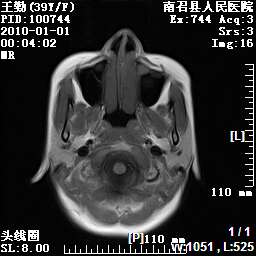

以下是引用随光逐影在2010-1-22 9:03:00的发言:[br]考虑左侧中颅窝(蝶骨翼区)脑膜瘤侵犯蝶骨翼并突入左侧眼眶。

以下是引用水过无痕在2010-1-22 14:55:00的发言:[br]一、定位:颅外占位;二、定性:恶性可能性大;三、组织来源:来源于左侧眼外直肌或其他部位;考虑为:横纹肌肉瘤>转移瘤>脑膜瘤.